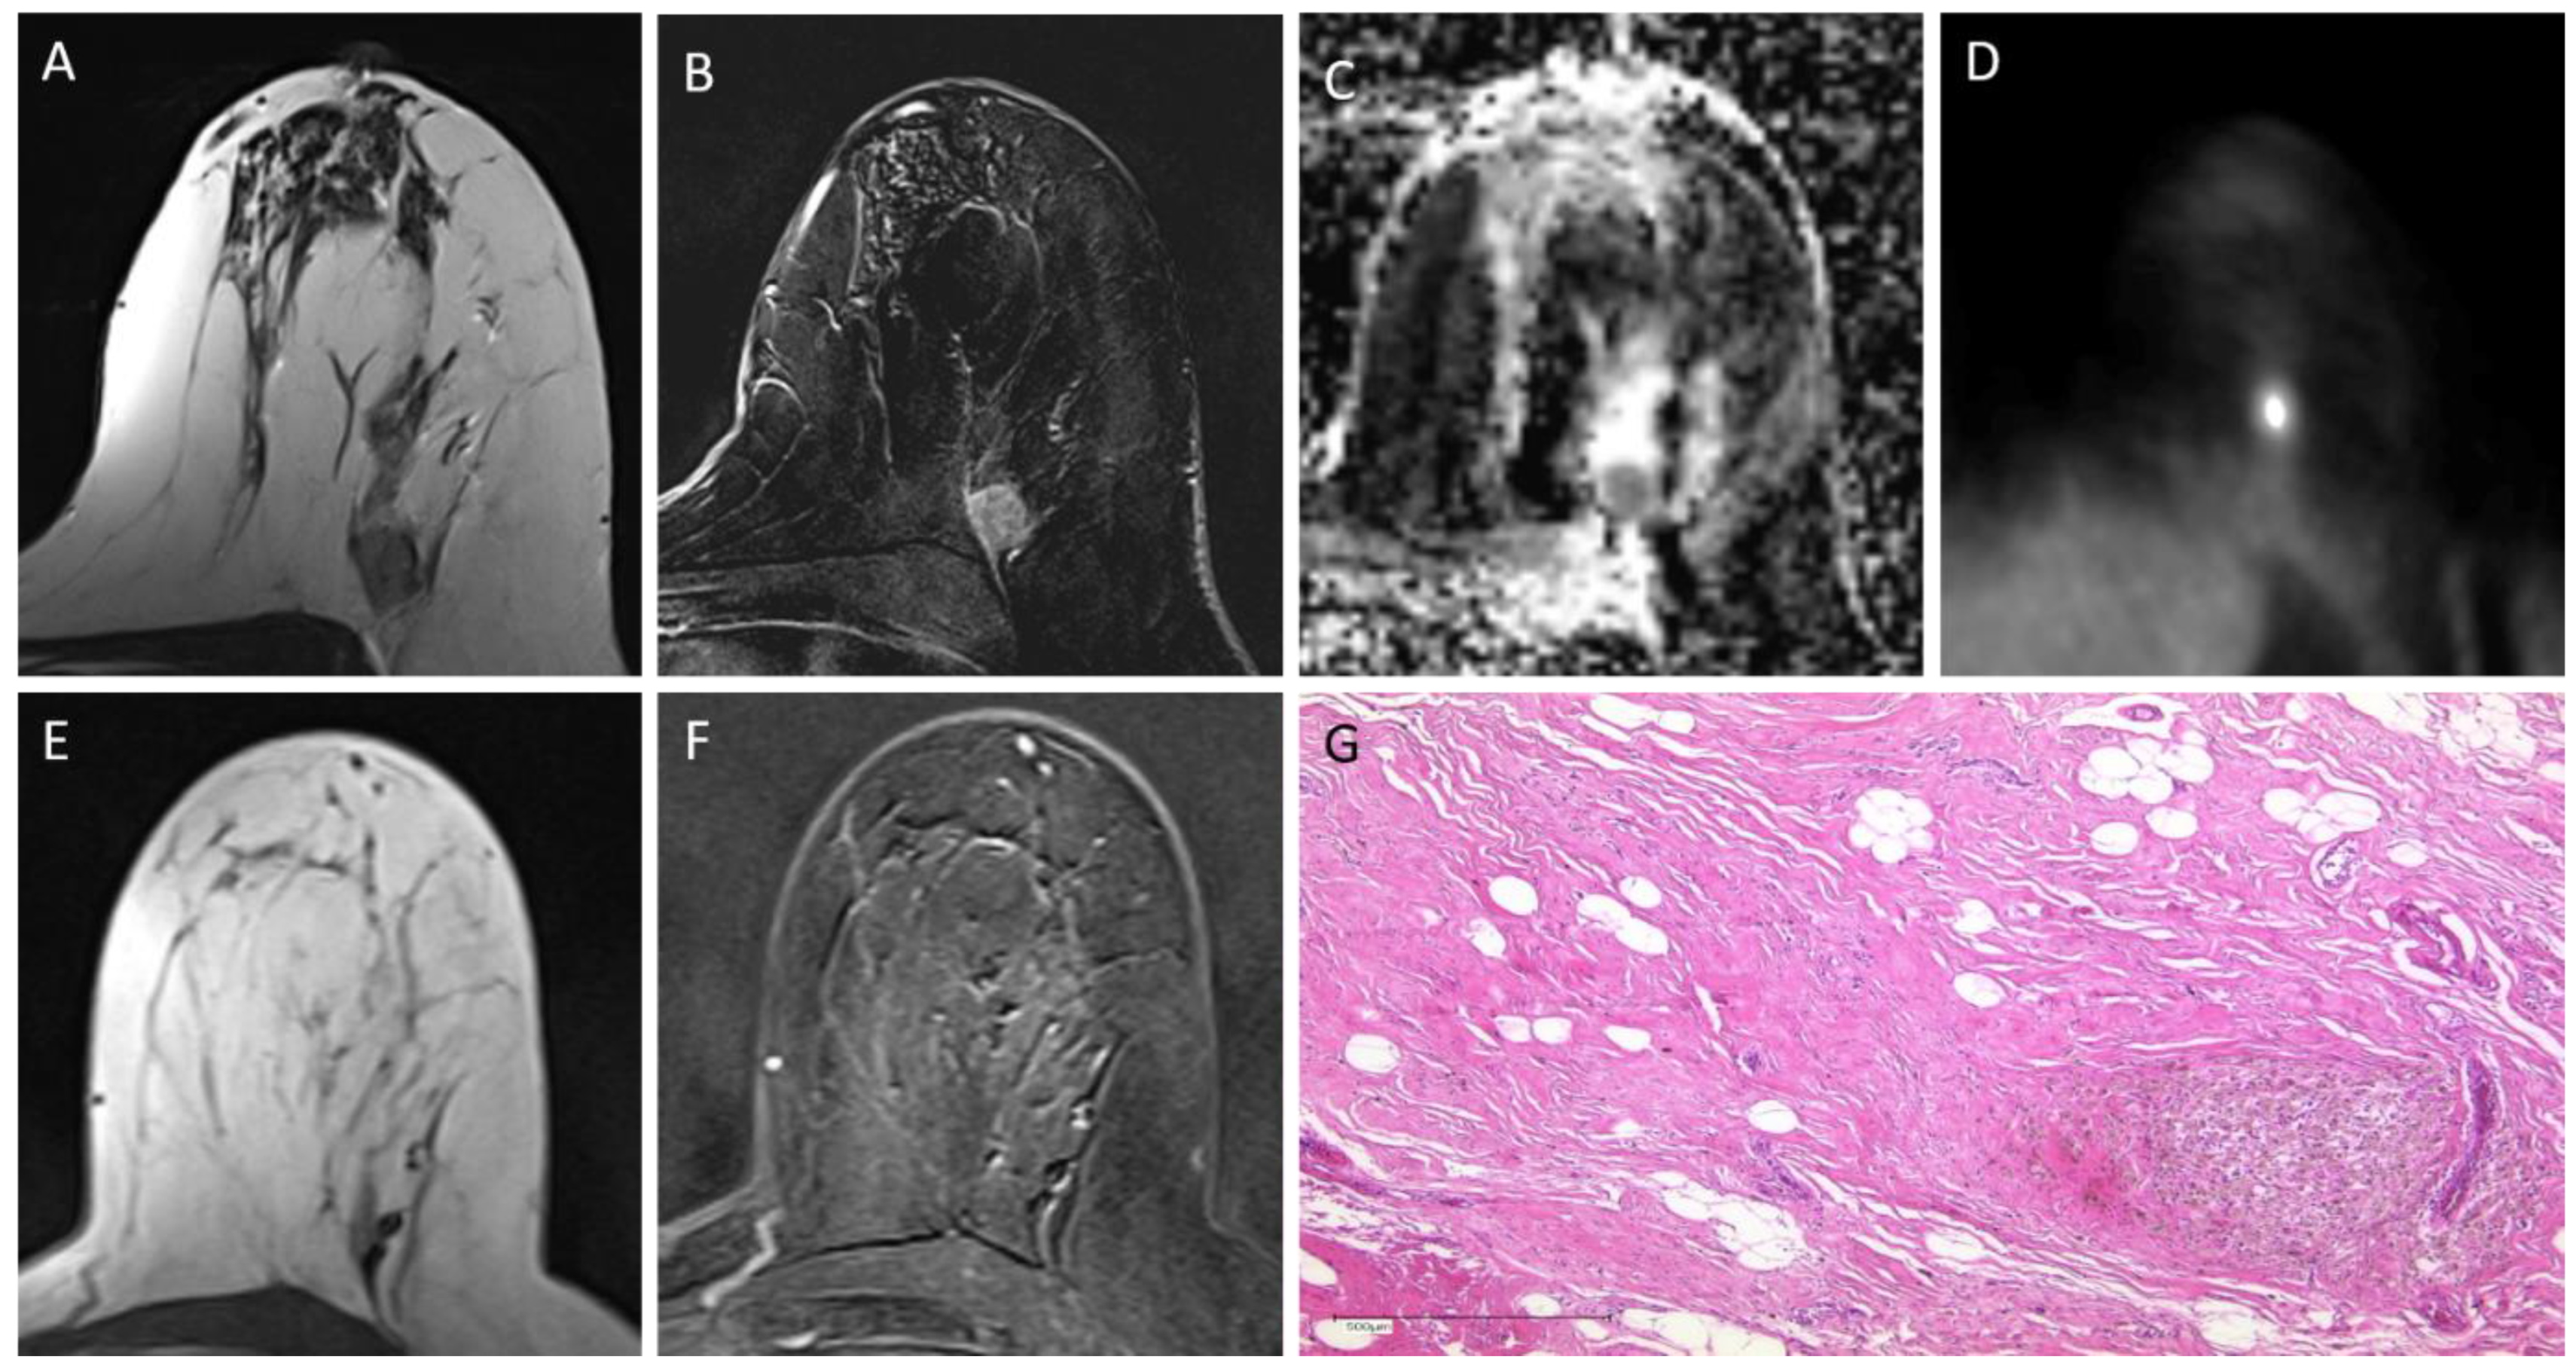

2.2. PET/MRI

2.3. Image Analysis